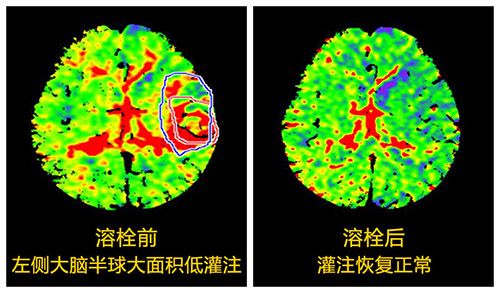

張靜波聽完電話直奔醫(yī)院,同時(shí)她用手機(jī)指揮臨床一線醫(yī)生進(jìn)行應(yīng)急處理。隨后張主任對(duì)患者進(jìn)行了多模式CT評(píng)估,判斷他的條件已符合溶栓治療,再加上自己多年的溶栓經(jīng)驗(yàn),她決定對(duì)其進(jìn)行溶栓治療。經(jīng)過一個(gè)多小時(shí)的精心溶栓,患者的上肢和下肢竟奇跡般的動(dòng)了起來,他終于脫離了生命危險(xiǎn),家屬因此非常感激。

2007年張靜波師從全國(guó)神經(jīng)科的領(lǐng)軍人物——北京天壇醫(yī)院院長(zhǎng)王擁軍教授,他是國(guó)家最早“十一五”研究項(xiàng)目的領(lǐng)頭人,她跟隨王擁軍教授學(xué)習(xí)并參與其研究項(xiàng)目。經(jīng)過自身的艱苦奮斗以及團(tuán)隊(duì)的精誠(chéng)合作,終于在2007年她在國(guó)內(nèi)率先開展了《多模式CT指導(dǎo)的擴(kuò)大時(shí)間窗急性腦梗死溶栓治療》研究,并在中華神經(jīng)科雜志率先發(fā)表,填補(bǔ)了國(guó)內(nèi)空白,該論文2013年獲中華神經(jīng)科雜志優(yōu)秀論文三等獎(jiǎng)。共發(fā)表論文20余篇,其中SCI一篇;主編著作1部,參編著作3部,大連市科技進(jìn)步二等獎(jiǎng)一項(xiàng);遼寧省科技進(jìn)步三等獎(jiǎng)一項(xiàng)。自2007年承擔(dān)國(guó)家“十一五”課題協(xié)作項(xiàng)目、國(guó)家新藥平臺(tái)、衛(wèi)生行業(yè)科研專項(xiàng)、“十二五”、“十三五”等多項(xiàng)研究課題,都取得了矚目的成就,并獲科研經(jīng)費(fèi)150余萬元。